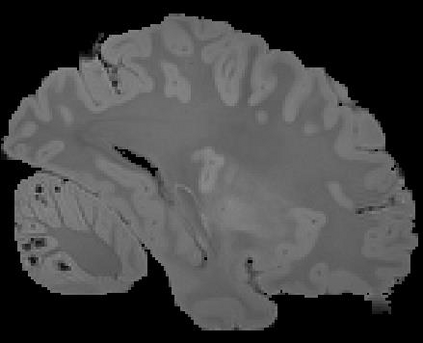

In neuroimaging, MRI tissue properties characterize underlying neurobiology, provide quantitative biomarkers for neurological disease detection and analysis, and can be used to synthesize arbitrary MRI contrasts. Estimating tissue properties from a single scan session using a protocol available on all clinical scanners promises to reduce scan time and cost, enable quantitative analysis in routine clinical scans and provide scan-independent biomarkers of disease. However, existing tissue properties estimation methods - most often $\mathbf{T_1}$ relaxation, $\mathbf{T_2^*}$ relaxation, and proton density ($\mathbf{PD}$) - require data from multiple scan sessions and cannot estimate all properties from a single clinically available MRI protocol such as the multiecho MRI scan. In addition, the widespread use of non-standard acquisition parameters across clinical imaging sites require estimation methods that can generalize across varying scanner parameters. However, existing learning methods are acquisition protocol specific and cannot estimate from heterogenous clinical data from different imaging sites. In this work we propose an unsupervised deep-learning strategy that employs MRI physics to estimate all three tissue properties from a single multiecho MRI scan session, and generalizes across varying acquisition parameters. The proposed strategy optimizes accurate synthesis of new MRI contrasts from estimated latent tissue properties, enabling unsupervised training, we also employ random acquisition parameters during training to achieve acquisition generalization. We provide the first demonstration of estimating all tissue properties from a single multiecho scan session. We demonstrate improved accuracy and generalizability for tissue property estimation and MRI synthesis.